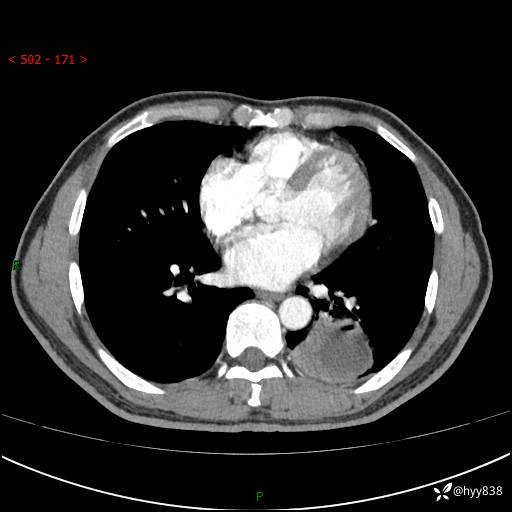

胸部CT平扫

增强

下肺占位,穿刺明确病理